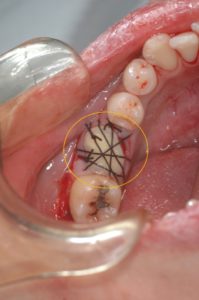

抜歯した親知らずを移植して縫合しました。特別な固定は不要です。